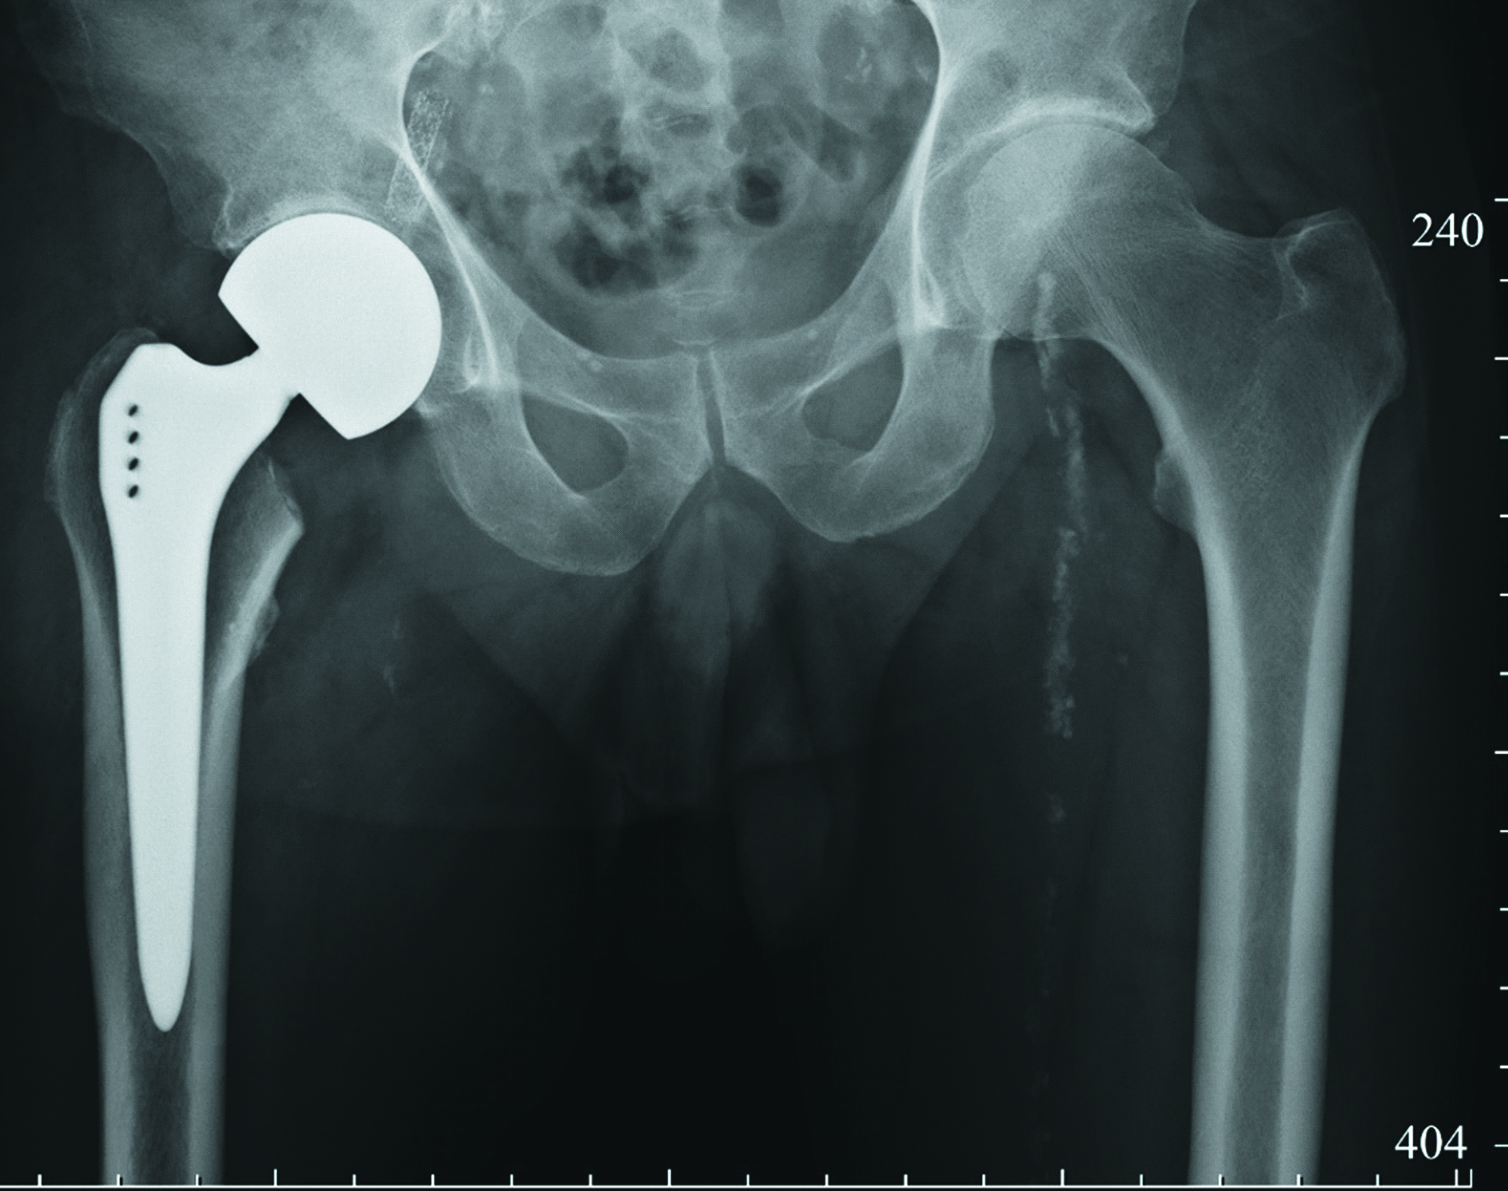

На следующий день после артропластики выполнена контрольная рентгенография правого тазобедренного сустава (рисунок 2).

Рисунок 2. Рентгенограмма правого тазобедренного сустава пациента З., сутки после операции.

Figure 2. X-ray of the right hip joint of patient Z., one day after surgery.